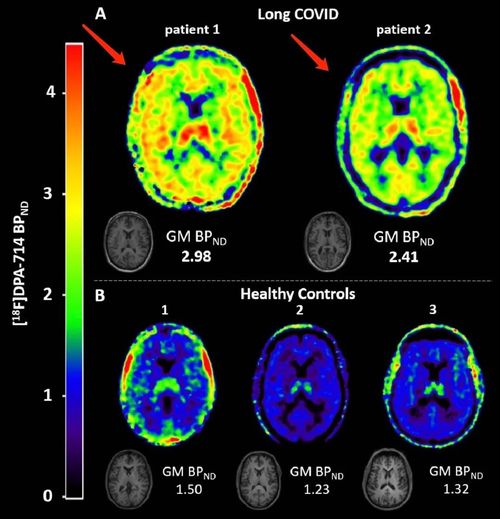

该研究采用了正电子发射断层扫描(PET)观察了长新冠患者大脑中的[18F]DPA-714水平,从而评估了患者大脑神经中小胶质细胞激活炎症。[18F]DPA-714是PET示踪剂,是一种高亲和力转运体蛋白(TSPO,一种在脑中活化的小胶质细胞和巨噬细胞中表达的线粒体外膜蛋白,作为神经炎症标志物)配体。[18F]DPA-714可用于评估各种神经炎症模型和脑肿瘤模型中的炎症特异性成像。

研究者对2名长新冠患者进行了动脉血样动态60分钟[18F]DPA-714PET扫描。为了评估示踪剂代谢,研究者将两名长新冠患者血液中的[18F]DPA-714代谢物与所有其他可用受试者的血液中的代谢物进行了比较。他们评估了全血中的活性浓度,校正了来自动脉血样本的注射活性和示踪母体分数。

研究发现,长新冠患者1在所有脑区的[18F]DPA-714结合严重升高。其2T4k_VB模型获得的全脑灰质定量BPND(=k3/k4)相对于健康对照受试者平均增加了121%。长新冠患者2的[18F]DPA-714结合也升高了,从2T4k_VB模型获得的全脑灰质BPND(=k3/k4)相对于健康对照受试者平均增加79%。